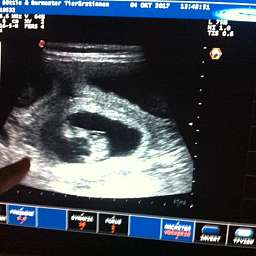

4.10.2017, 35.Tag: Der Ultraschall brachte 5 kleine Wunder zutage. Gesund und munter mit Herzschlag und Bewegung. Elise meisterte alles mit Bravour. Mit Ruhe, Vertrauen und Engelsgeduld ließ sie alles über sich ergehen. Ich bin sehr stolz auf unsere Kleine. Es sind also mindestens 5 Welpen unterwegs. Schaut doch mal: